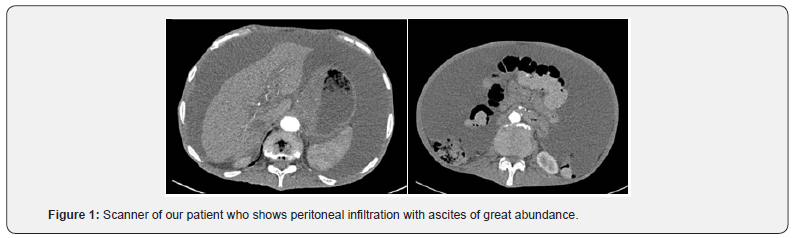

A morphological assessment based on an abdominopelvic CT scan confirmed the existence of homogeneous ascites andhepatomegaly without evidence of portal hypertension or ovarian mass.

The myelogram was inconclusive. A bone marrow biopsy showed diffuse medullary infiltration by plasma cells with thepresence of 20% dystrophic plasma cells (Figure 1). The diagnosis of MM with peritoneal involvement was made. The patient was transferred to the hematology department for specialized management (Figure 2).